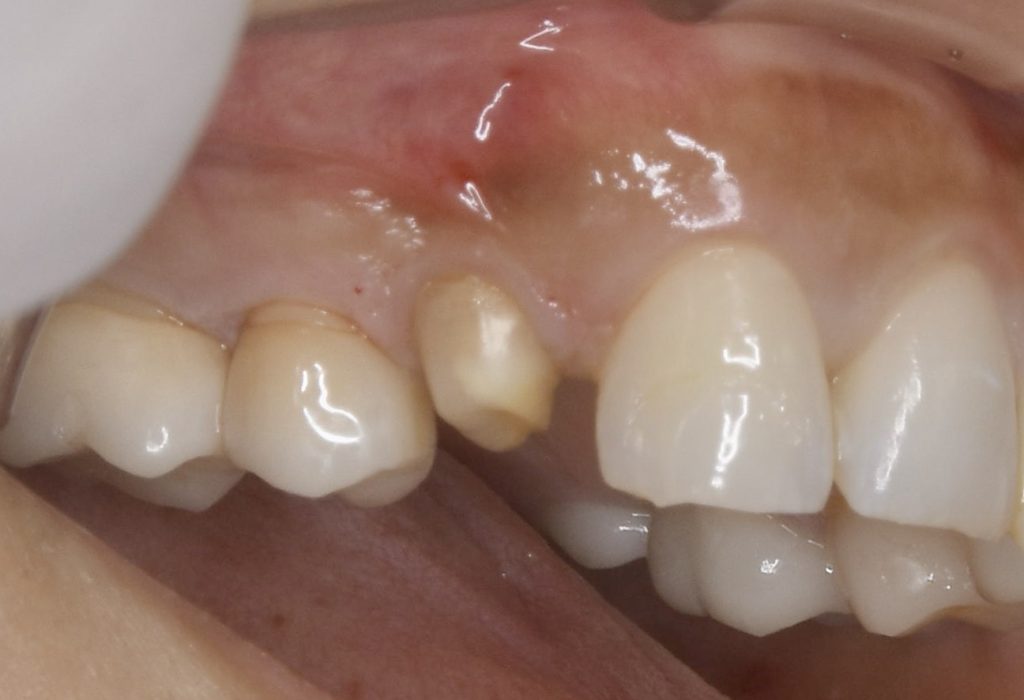

下記の症例は7年前の来院時に外部吸収を起こしていた為、患者さんに抜歯を勧めていました。

その時は、さほど自覚症状もなく、経過観察となりましたが、今回は被せ物が取れ、口臭がするという事で久しぶりに当医院に来院していただきました。

神経がないので痛みというより違和感程度でしたが、抜歯に同意していただき、抜歯と同時にインプラント治療を行い、できるだけ負担を減らし治療期間を短縮する計画を立てました。